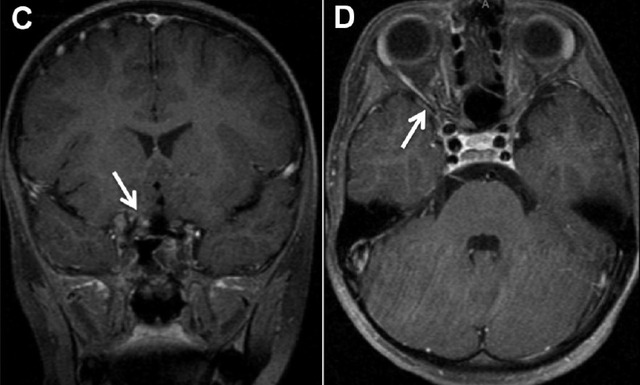

患者,男,6 岁,右眼视力光感,瞳孔对光反应缺陷,眼底照相显示扩张扭曲的眼底血管(图 A)。OCT 显示视乳头与黄斑间的视网膜下层有积液层(图 B 箭头处)。MRI 图像显示视神经管或眶尖有增强(图 C 箭头处),在后眼眶匍匐的小血管有流空现象(图 D 箭头处)。这些眼部与脑部的病理变化与 Wyburn-Mason 综合征有关。

图 A 为眼底照相图